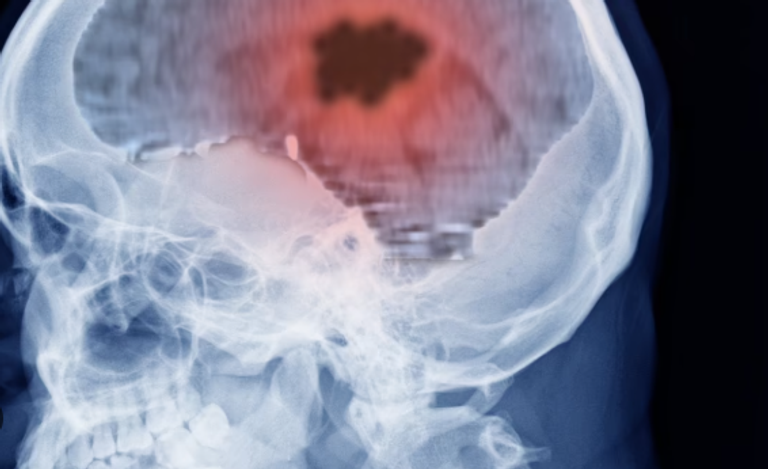

الاختبار يتم عن طريق وضع يد فوق الأخرى وتقليب اليد العلوية بسرعة للأعلى والأسفل عدة مرات، ثم تكرار الحركة باليد الأخرى، وعدم القدرة على تنفيذ الحركة بسلاسة قد يشير إلى حالة تُعرف بـ"عسر التناسق الحركي"، وهي علامة على وجود مشكلة في المخيخ، مثل ورم دماغي أو تلف في الأعصاب.

وتشمل أسباب الفشل في أداء الحركة أوراما في المخ، أو أمراضا عصبية مثل التصلب المتعدد، ورغم أن الأورام الحميدة لا تنتشر، فإنها قد تشكل خطرا إذا نمت في مناطق حساسة من الدماغ.

يُذكر أن أكثر من 12,000 شخص في بريطانيا يتم تشخيصهم بأورام دماغية سنويا، ونصفهم تقريبا يعانون من أورام سرطانية، وتُعد أورام الدماغ من أكثر أسباب الوفاة شيوعا لدى الأطفال والبالغين دون سن الأربعين.